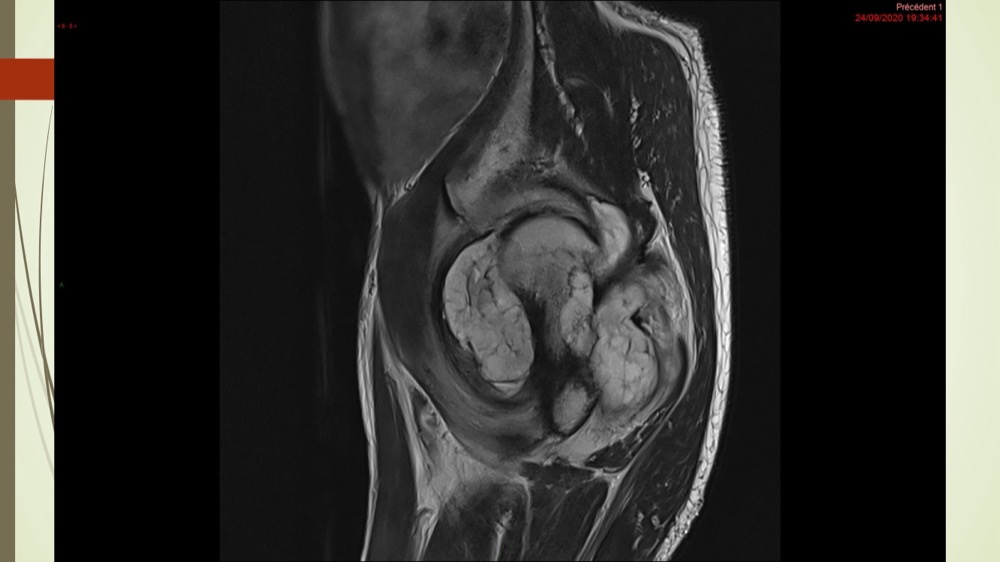

Coxalgie traînante

Kévin Mahé 29/06/2022